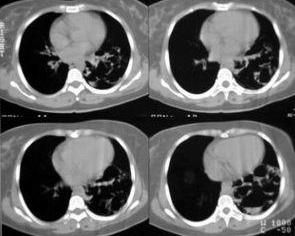

先天性支气管源性囊肿也被称为支气管源性囊肿,指以支气管组织成份为囊壁、内含粘液或气体的先天性囊肿,曾被称为先天性囊性支气管扩张或先天性支气管源性囊肿。目前认为是肺胚胎发育过程中,大多数发生在26~40天,是气管发育的最活跃期,与肺隔离症相似,肺芽远端小块肺实质细胞在其分支过程中与之脱离,异位发育而成,但与肺隔离症不同,它没有进一步发育异常胚芽出现的时间的早晚,决定了其部位。异常发育出现较早,肺胚芽尚在大气管附近发育时,囊肿位于纵隔或肺门,称为支气管囊肿;而异常发育出现较晚者,异常胚芽易于停留在肺内,囊肿多位于肺内,称为肺囊肿。